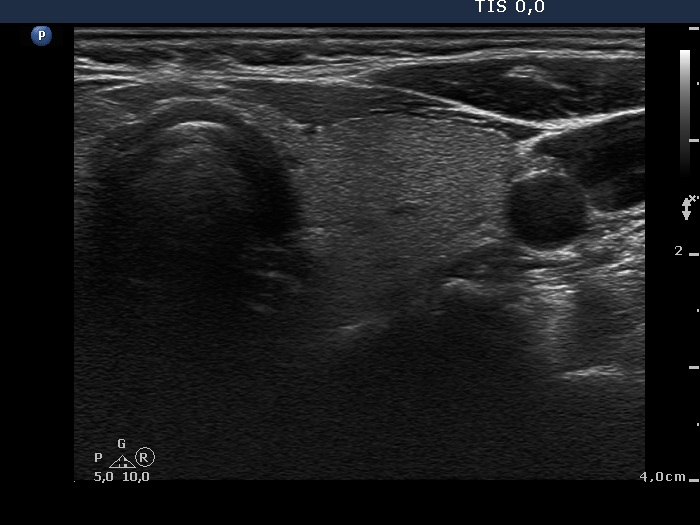

Oxyphilic adenoma - Case 6. (ultrasonographic picture 6)

Left lobe, horizontal scan. This lobe is intact.